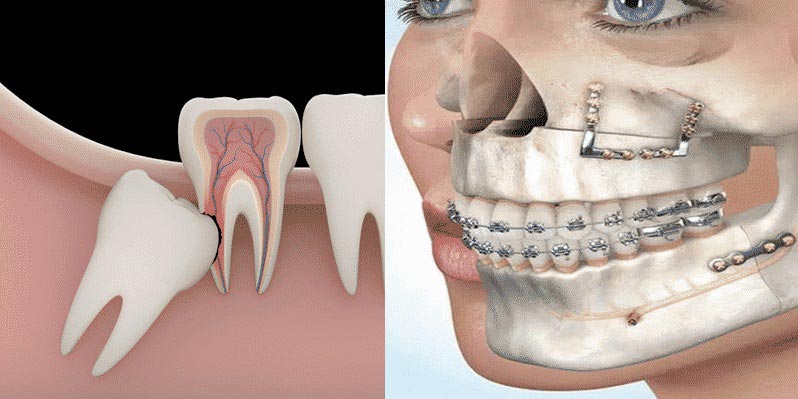

Realizamos cirugías orales y maxilofaciales como extracciones simples y complejas, cordales incluidos, exposición de dientes retenidos, frenillos y procedimientos preprotésicos.

Todas las intervenciones se planifican con imágenes diagnósticas y se realizan con protocolos estrictos de bioseguridad para tu tranquilidad.